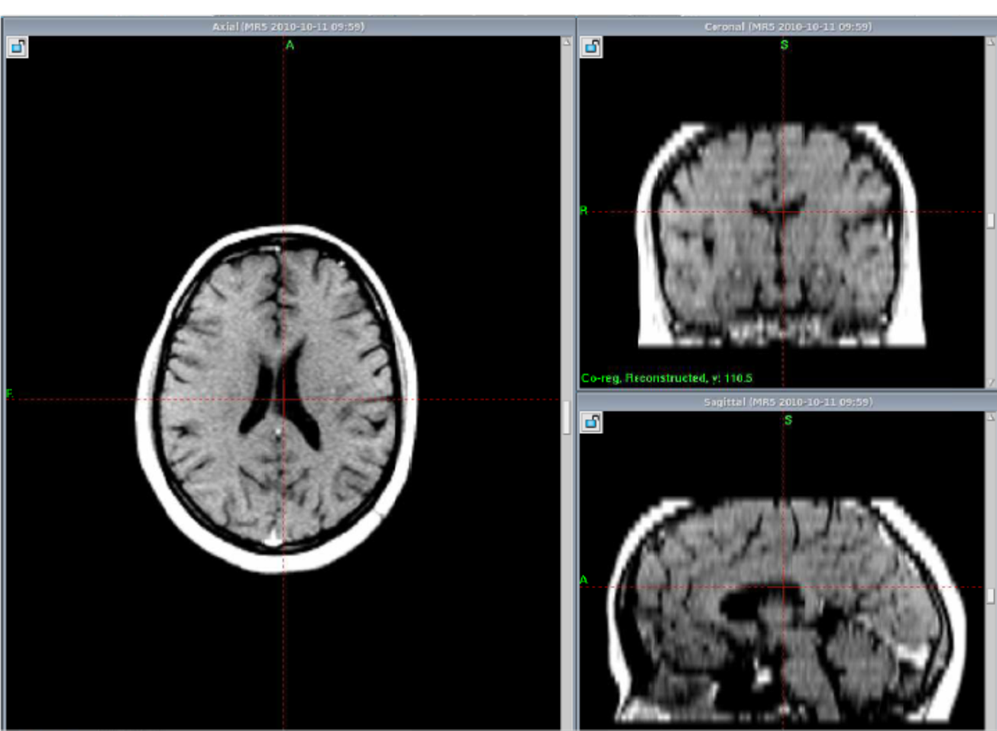

Complete resolution after one year of Gamma knife Treatment.

At GKRS                             After one year                              After Two years